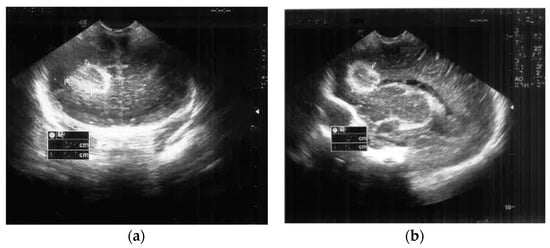

2. Case Presentation